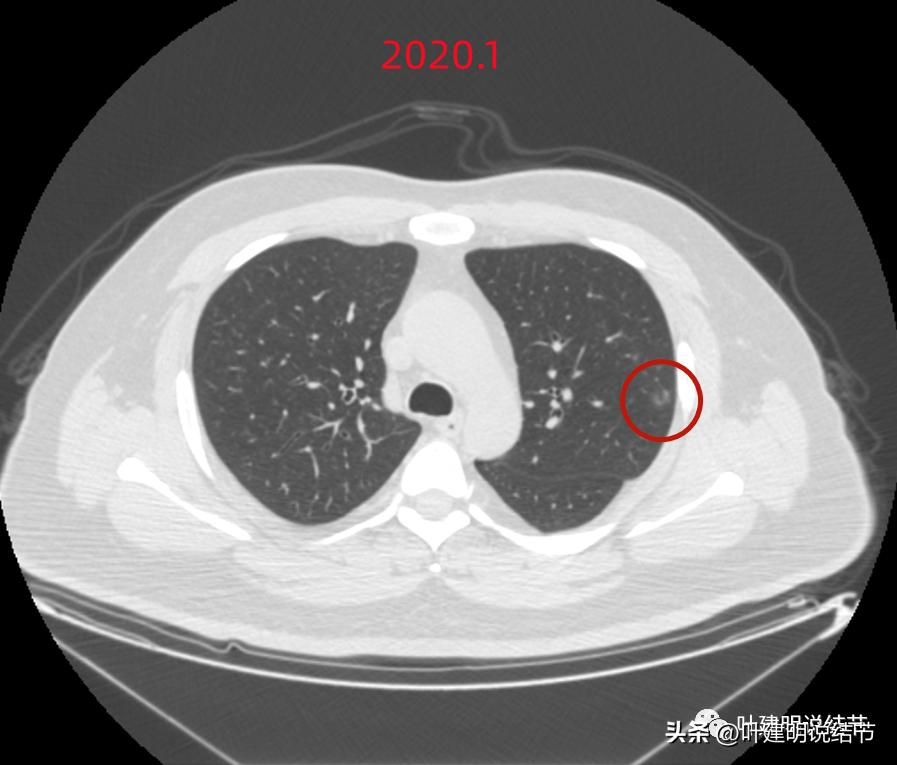

我看后的第一个感觉是,怎么这么明显像恶性的结节,还没有开刀呢?现在2年多过去了,不知道进展到如何,还有没有手术机会?第二个感觉是这个多个病灶集中在左上叶,其他肺上不明显,感觉有点怪怪的,多原发癌一般不同叶的更常见些。我想先再看看细节信息,所以又逐幅图再仔细看了一遍:

这个病灶也仍考虑是恶性范畴的,只是风险较病灶2与病灶3为低。也就是说看了细节与所有层面的信息,仍基本上认为四个病灶都是肿瘤范畴的,病灶1与病灶4大概浸润前病变可能性大,病灶2与病灶3则至少微浸润,基本以浸润性腺癌可能性大,不过不太能理解的有两点:一是病灶太集中;二是有的层面似有卫星灶。当然病灶2与病灶3感觉磨玻璃的成分偏少了些,也可作为疑惑之处。

后续再看2022年8月的CT图像,有点惊掉下巴的感觉:

左上叶的病灶1、2、3都没有了!!!完全没有了!那当然说明是炎症性的,居然全部吸收了!

但左上病灶4仍在,形态也没有明显变化,无好转,也无明显进展。这是肿瘤性质的吗?虽然存在2年多了,但因为它的兄弟们都不见了,让我对它认定的肿瘤范畴也产生了怀疑,也许是纤维增生而已呢!